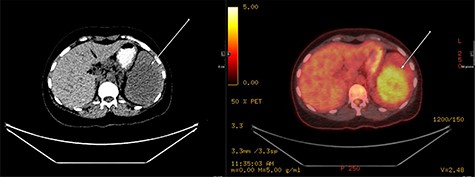

A repeat contrast-enhanced CT scan 21 months later showed an increase in size of the lesion to 8.0 × 7.2 × 6.6 cm (Fig. 4). Positron emission tomography (PET) CT demonstrated the mass to be moderately hypermetabolic with a standardized uptake value (SUV) of 4.7 (Fig. 5).

The post-contrast CT axial image showing central hypodense splenic lesion in portovenous phase (arrow—right image) which becomes isodense on delayed images (arrow—left image).

PET fused axial image with corresponding low-dose unenhanced CT image (left); the lesion is showing moderate FDG uptake (arrow).